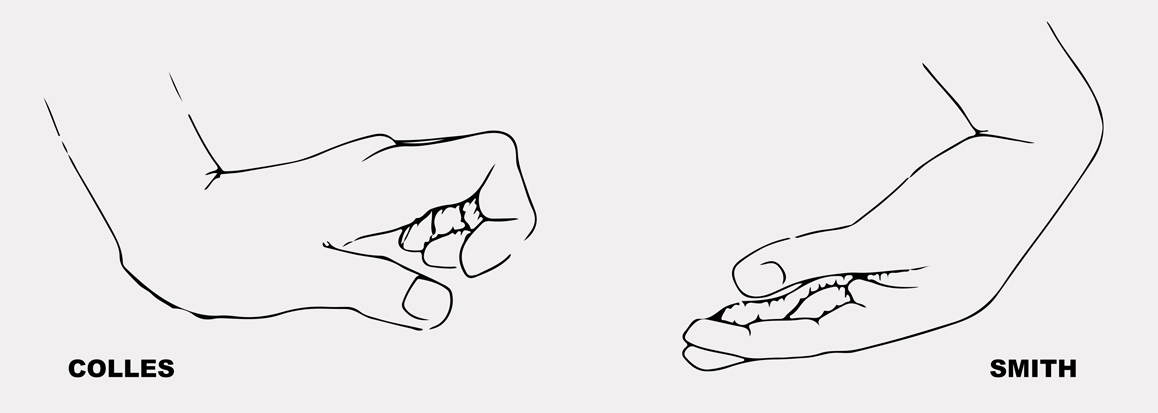

Złamaniem nadgarstka potoczenie nazywamy dystalne złamanie kości promieniowej. Do urazu dochodzi najczęściej na skutek upadku na wyprostowaną bądź zgiętą rękę w trakcie uprawiania sportu, jazdy na nartach bądź na skutek wypadku komunikacyjnego. W zależności od tego czy do urazu dochodzi na skutek nadmiernego zgięcia lub wyprostowania ręki, wyróżniamy złamanie Collesa i Smitha. Złamania nadgarstka nie sposób nie zauważyć. Natychmiast pojawia się ból i ograniczenie ruchomości stawu, a także obrzęk i deformacje.

• złamanie dystalne kości promieniowej (złamanie Collesa, Smitha) • po przebytych urazach stawu promieniowo nadgarstkowego • w zapaleniach kaletek ścięgnistych, • w zmianach przeciążeniowych, zwyrodnieniowych i zapalnych • skręcenie stawu nadgarstkowego • zwichniecie stawu nadgarstkowegoTo jest wyrób medyczny.